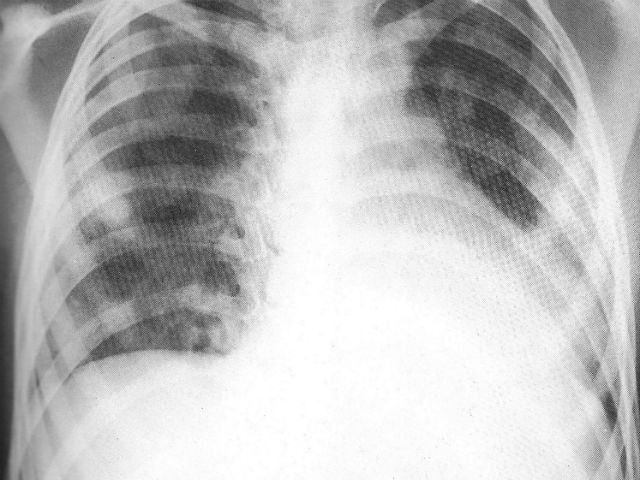

ROMA – Ogni 25 secondi nel mondo un bambino muore di polmonite, per un totale 3.400 decessi al giorno.